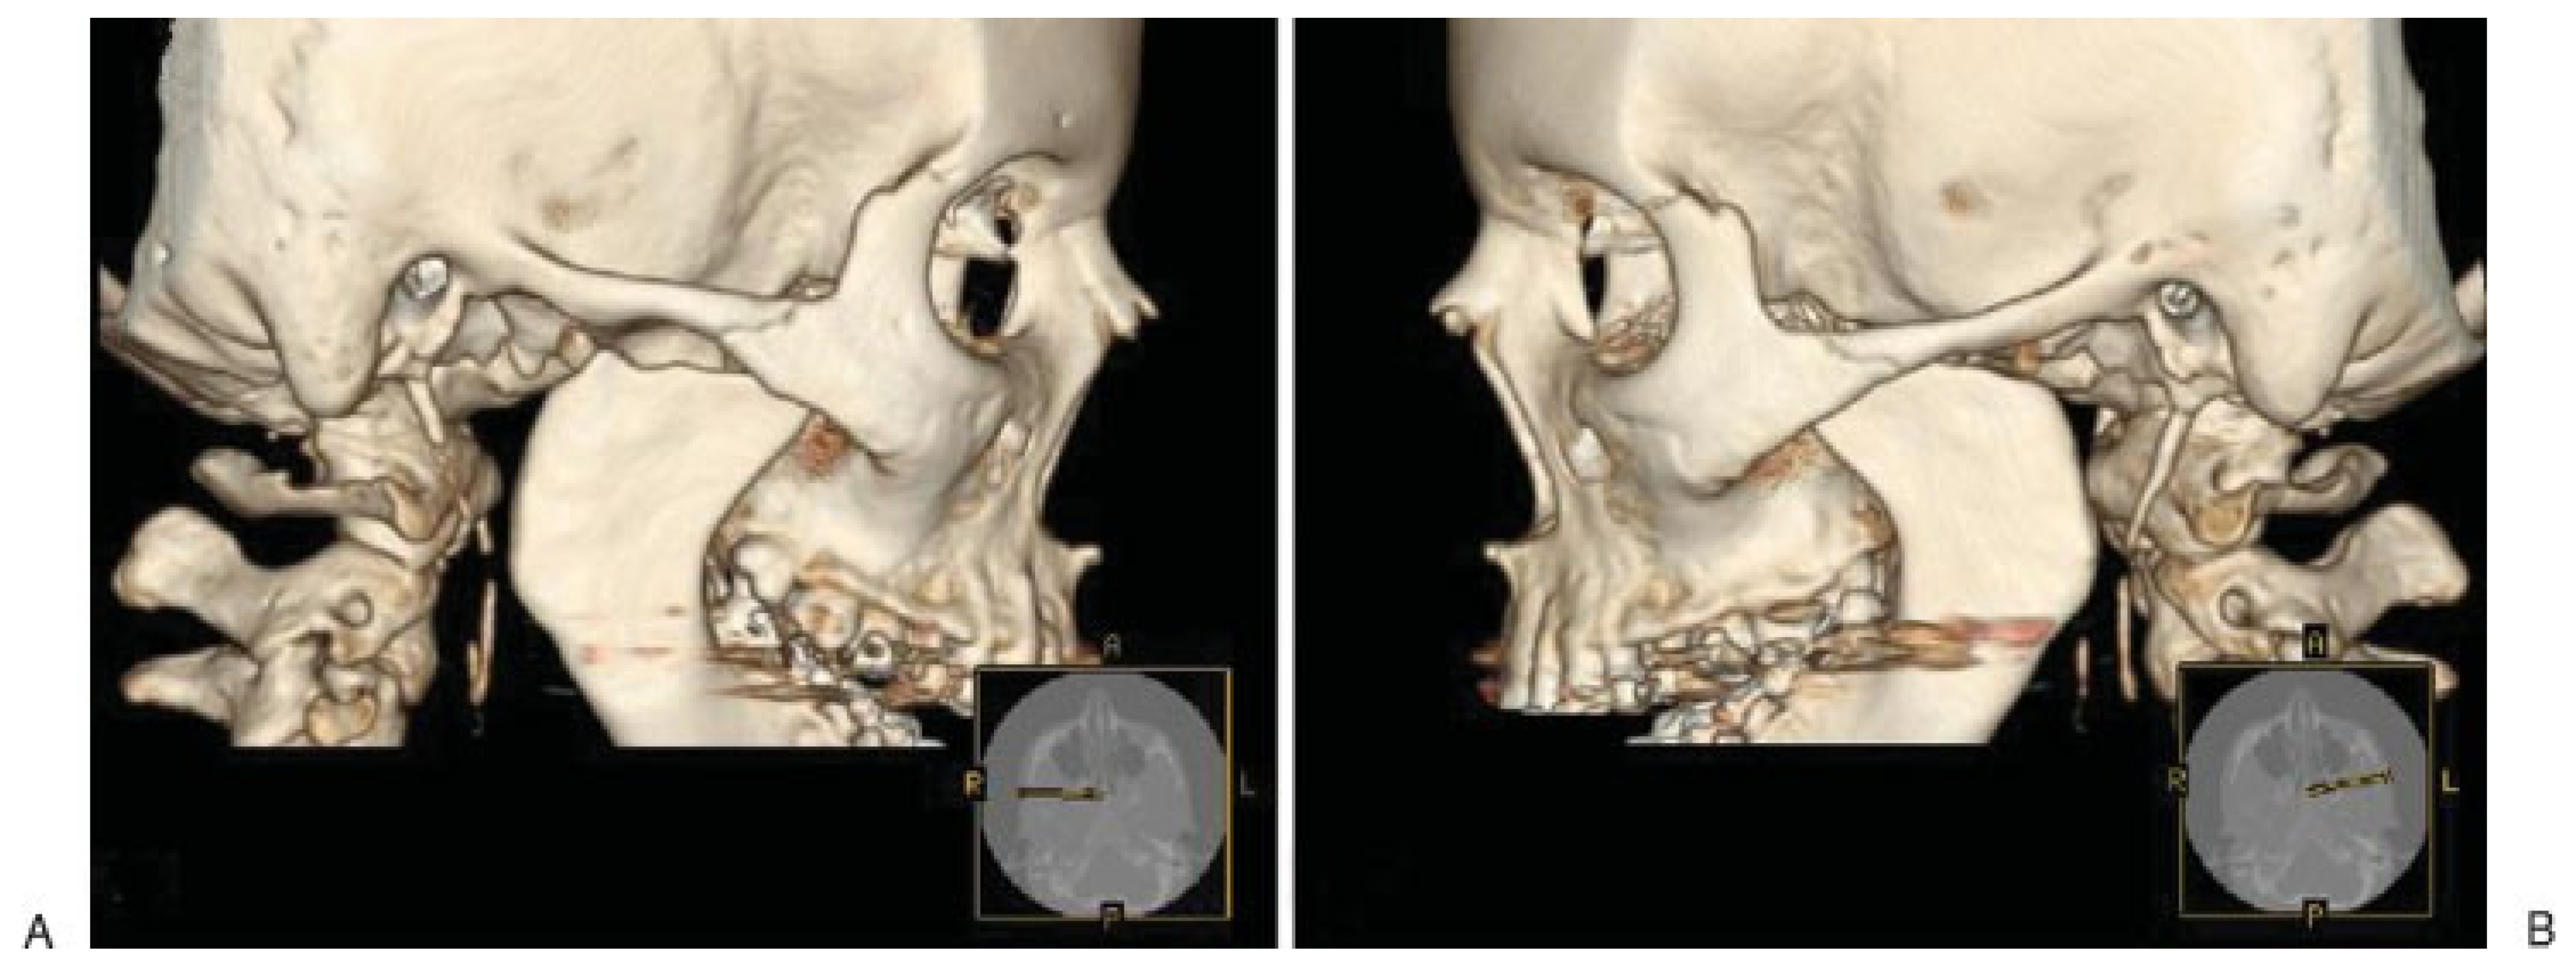

Radiological Examination